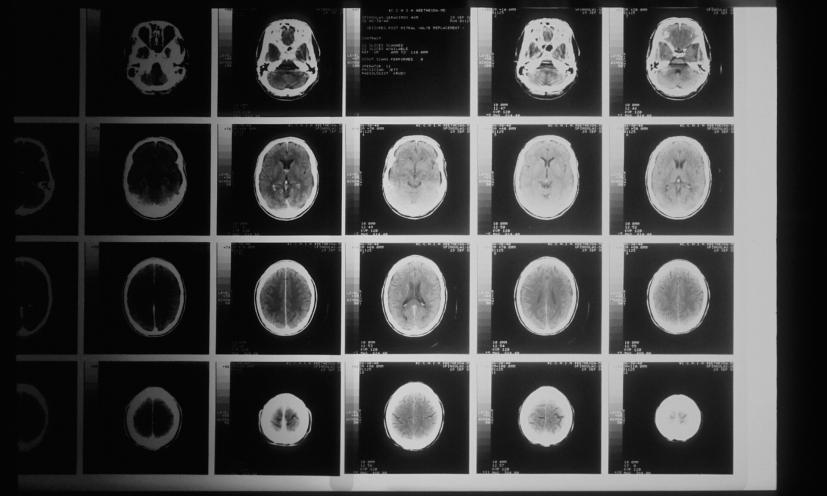

Το 2021, οι υγειονομικές αρχές του New Brunswick προειδοποίησαν ότι περισσότεροι από 40 κάτοικοι έπασχαν από ένα πιθανό άγνωστο νευρολογικό σύνδρομο, με συμπτώματα παρόμοια με εκείνα της εκφυλιστικής εγκεφαλικής διαταραχής, που ονομάζεται Creutzfeldt–Jakob.

Τα συμπτώματα ήταν ποικίλα και κατά περιπτώσεις έντονα. Σε ορισμένους ασθενείς άρχισαν να τρέχουν σάλια και άλλοι ένιωθαν σαν να σέρνονται έντομα στο δέρμα τους. Ωστόσο, έναν χρόνο αργότερα, μία ανεξάρτητη επιτροπή εποπτείας που δημιουργήθηκε από την επαρχία διαπίστωσε ότι στην ομάδα των ασθενών πιθανότατα είχε δοθεί λανθασμένη διάγνωση.